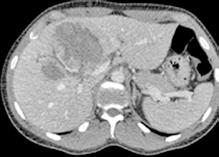

Se solicita una Ecografía abdominal donde se visualiza una masa hepática de aproximadamente 12 cm y directamente se solicita una Tomografía Computarizada (TC) urgente. Se confirma la masa hepática, que mide 13x11x10 cm, con signos de sangrado reciente pero sin sangrado activo.

Localizada en los segmentos VII, V y parte del IV, entre las venas suprahepáticas (VSH) derecha y media, contactando con ellas en su origen. Caudalmente llega hasta la bifurcación hiliar, cercano a la bifurcación portal. Esta masa presenta una captación periférica en fase arterial y algo más isodensa en fase venosa y tardía, con un área central heterogénea e hipodensa en estas últimas fases. Con este comportamiento radiológico, se establece un diagnóstico de sospecha de hepatocarcinoma fibrolamelar o adenoma. Como variante anatómica, se objetiva una arteria hepática que nace de la arteria mesentérica superior (Figura 1). El paciente es ingresado en Digestivo para estudiar la lesión. Se realiza una Resonancia Magnética (RM) y se establece un diagnóstico de sospecha de hepatocarcinoma fibrolamelar (Figura 2). Se descartó una biopsia por el riesgo de resangrado que presentaba. La alfafeto proteína solicitada durante el ingreso fue normal. Dado que se trata de una lesión hepática sintomática y que ha presentado un sangrado, está indicada la resección de la lesión, pero su tamaño y localización lo impiden. La lesión está tan cerca de las VSH que resulta imposible disecarlas y seccionarlas con seguridad, siendo imposible la cirugía. Se comenta el caso en el comité multidisciplinar y se decide embolizar la tumoración con el objetivo de evitar un nuevo sangrado y disminuir su tamaño para separarla de las estructuras vasculares. Se cateteriza la arteria hepática, desde la mesentérica superior. Se emboliza con micropartículas

Figura 2 (A y B).

RM: Gran masa hepática localizada en segmentos VII, V y parte del IV. Comportamiento radiológico característico de hepatocarcinoma.

A) T1, imagen hipointensa entre VSH derecha y media.

B) T2, lesión hiperintensa con centro hipointenso.

Figura 4.

TC realizado tras las dos embolizaciones arteriales. Vemos cómo la lesión ha disminuido considerablemente de tamaño y ahora está más alejada de las VSH y de la cava. Esto permite la ligadura de las VSH en su confluencia con la cava. Inicialmente no habría sido posible por su cercanía y tamaño.